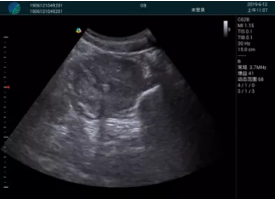

清晰顯示孕囊,通過軟件包計(jì)算孕齡7w+6d

M20實(shí)時(shí)引導(dǎo),術(shù)中清晰顯示孕囊被破壞和抽吸針的過程,清晰顯示吸引針

抽吸結(jié)束后縱切子宮,孕囊已被完全抽吸,未見明顯殘留

橫切子宮,發(fā)現(xiàn)右側(cè)宮腔靠近宮角處有少許脫模樣殘留

M20引導(dǎo)下,抽吸針找到右側(cè)宮角處再次清掃

二次抽吸后再次進(jìn)行超聲檢查,宮腔未見殘留,宮腔線清晰顯示